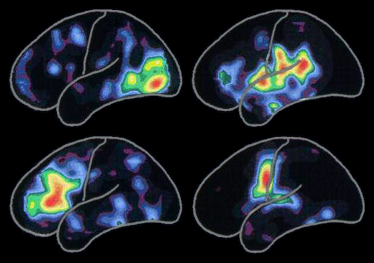

МРТ мозга при различных операциях:

по порядку:

чтение слов

прослушиванием слов

размышление о словах

произнесение слов